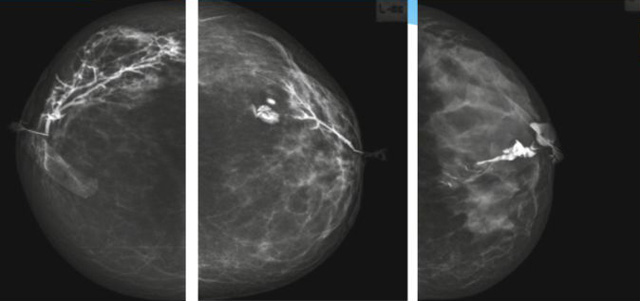

乳腺導(dǎo)管內(nèi)乳頭狀瘤分為以下兩個(gè),位于乳暈區(qū)大導(dǎo)管的中央型乳頭狀瘤,起源于末梢導(dǎo)管小葉單位的外周型乳頭狀瘤。外周型乳頭狀瘤常常沒有明顯的的臨床表現(xiàn),常因X線或乳腺超聲設(shè)備檢查發(fā)現(xiàn)。重點(diǎn)要關(guān)注的是中央型乳頭狀瘤,發(fā)生于任何年齡的女性,以40~50歲者居多。它表現(xiàn)為:單側(cè)乳頭溢液,特別是血性溢液少數(shù)病人可在乳暈區(qū)觸及腫塊。從病理學(xué)上面講表現(xiàn)為導(dǎo)管上皮和間質(zhì)增生形成有纖維脈管束的乳頭狀結(jié)構(gòu)。這是它一個(gè)病理學(xué)上的表現(xiàn)。它的超聲表現(xiàn)為:病變導(dǎo)管囊狀擴(kuò)張呈無回聲,內(nèi)可見乳頭狀低回聲或中等回聲。乳暈處的導(dǎo)管擴(kuò)張,管腔內(nèi)可見邊界清楚的,低回聲實(shí)性結(jié)節(jié)。外周型導(dǎo)管內(nèi)乳頭狀瘤可,表現(xiàn)擴(kuò)張為為低回聲的實(shí)性結(jié)節(jié),CDFI:部分腫瘤可顯示為軸心性的看到血流信號(hào)。乳腺增生癥:可見導(dǎo)管擴(kuò)張,內(nèi)無乳頭狀實(shí)性回聲,導(dǎo)管內(nèi)乳頭狀癌:囊內(nèi)乳頭狀癌病變較大,不規(guī)則,厚基底,血流豐富。以囊性為主的混合回聲,形態(tài)不規(guī)則,內(nèi)見實(shí)性低回聲實(shí)性低回聲可見少量血流,病理為囊內(nèi)乳頭狀癌。

乳腺超聲設(shè)備檢查的價(jià)值在哪里呢?它可以檢查發(fā)現(xiàn)乳暈周圍的各種病變,對(duì)于單側(cè)乳頭溢液、血性溢液的患者,超聲是首選的影像學(xué)檢查方法。注意:導(dǎo)管內(nèi)乳頭狀瘤可合并不典型增生或,導(dǎo)管內(nèi)乳頭狀癌,手術(shù)前懷疑時(shí)候,就應(yīng)該手術(shù)切除而不是用微創(chuàng)手術(shù)。